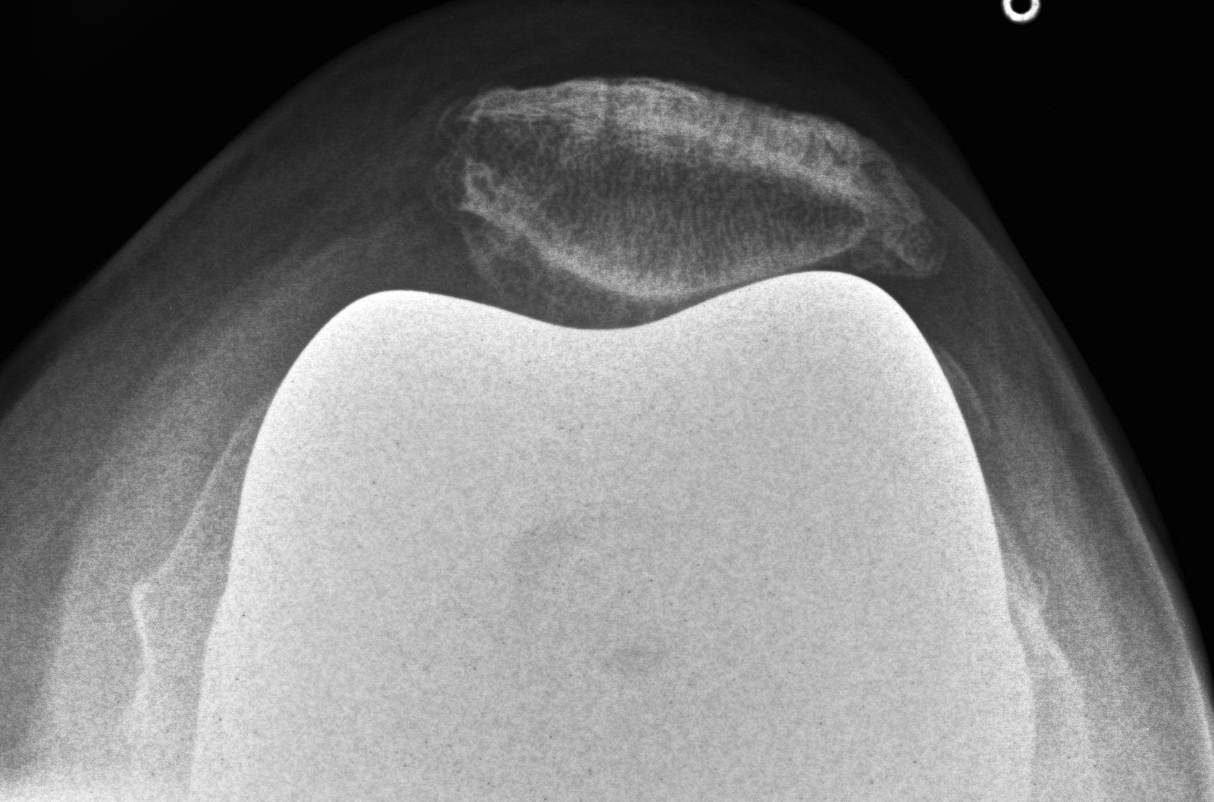

Xray

- skyline views

- lateral tilt / subluxation